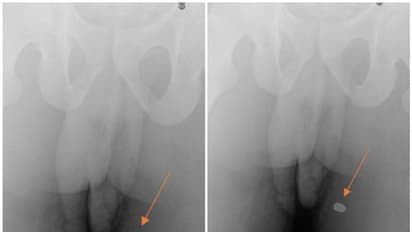

ആഫ്രിക്കന് അമേരിക്കന് വംശജനാണ് ലിംഗത്തിന് ശക്തമായ വേദനയെ തുടര്ന്ന് പ്രവേശിപ്പിക്കപ്പെട്ടത്. ലിംഗത്തിലെ ദ്വാരം വെടിയുണ്ട തുളച്ചുകയറി ഉണ്ടായതാണെന്നാണ് ഡോക്ടര്മാരുടെ പരിശോധനയില് തെളിഞ്ഞത്. ഇയാളുടെ ലിംഗത്തിന്റെ അഗ്രത്തിലൂടെയാണ് വെടിയുണ്ട തുളച്ചുകയറിയതായി കണ്ടെത്തിയത്. ലിംഗ്രാഗ്രത്തില് ദ്വാരം വീണതോടെ യുവാവിന് അതിശക്തമായ വേദന അനുഭവപ്പെട്ടു. ലിംഗോദ്ധാരണവും സാധാരണരീതിയില് നടക്കാതെയായി. ലിംഗത്തിന്റെ ഇടത് വശത്തേക്ക് മാത്രമായി വളഞ്ഞ നിലയിലാണ് ഉദ്ധാരണം നടന്നിരുന്നത്. എന്നാല് എക്സ്റേ പരിശോധനയില് ലിംഗം തുളച്ച് കയറിയ വെടിയുണ്ട ഇയാളുടെ തുടയില് തറച്ചതായി കണ്ടെത്തുകയായിരുന്നു.

'യൂറോളജി കേസ് റിപ്പോര്ട്സ്' എന്ന ജേണലിലാണ് യുവാവിന് സംഭവിച്ച അവസ്ഥയെ പ്രതിപാദിക്കുന്ന റിപ്പോര്ട്ട് അടങ്ങിയിട്ടുള്ളത്. ഇതിന് മുമ്പും ഇത്തരം കേസുകള് ശ്രദ്ധയില്പ്പെട്ടിട്ടുണ്ടെന്നാണ് യുവാവിനെ ചികിത്സിച്ച യൂറോളജിസ്റ്റ് ഡോ. റിച്ചാര്ഡ് വിനെ അറിയിച്ചത്. ലഹരിയുമായി ബന്ധപ്പെട്ട ശിക്ഷകളില് ഒന്നാണ് ഇതെന്നും അല്ലെങ്കില് ഒരുപക്ഷേ അബദ്ധത്തില് വെടിപൊട്ടിയതായിരിക്കാമെന്നുമാണ് ഡോക്ടര്മാരുടെ നിഗമനം. ലിംഗോദ്ധാരണം നടത്തുന്ന കോശങ്ങള്ക്ക് നാശം സംഭവിച്ചതിനാലാണ് യുവാവിന് ശരിയായ രീതിയില് ഉദ്ധാരണം നടത്താന് സാധിക്കാത്തതെന്നും ആറ് ആഴ്ചകള്ക്ക് ശേഷം മാതമെ യുവാവ് പൂര്വ്വസ്ഥിതിയിലേക്ക് എത്തുകയുള്ളൂ എന്നും ഡോക്ടര്മാര് അറിയിച്ചു.